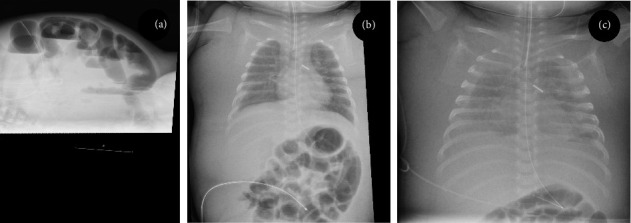

There are several causes of generalized edema in sick neonates. We describe two newborns that developed progressive and treatment-resistant generalized edema. We suggest this is due to impaired lymphatic flow from the thoracic duct as a result of a central venous catheter in the left subclavian vein.